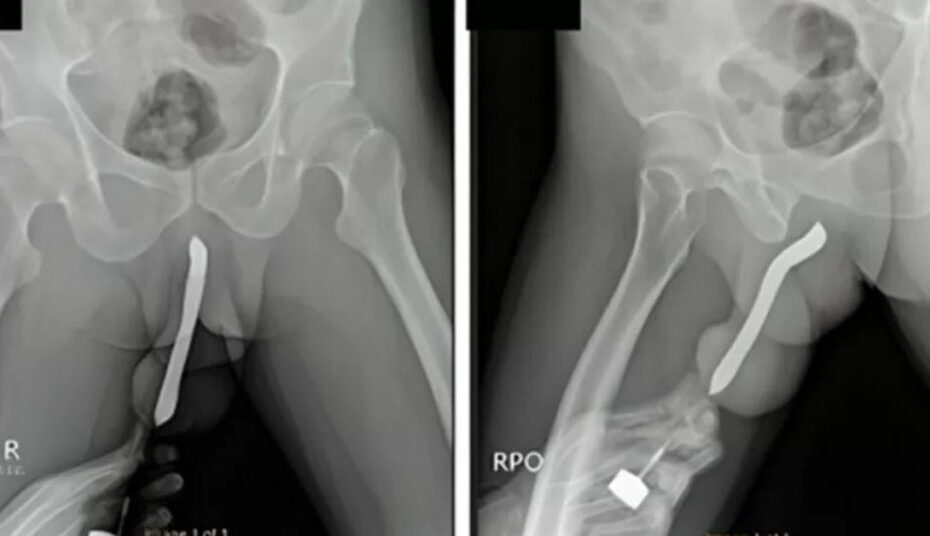

Um caso inusitado chamou a atenção da comunidade médica: um homem de 43 anos sofreu uma fratura no pênis após inserir uma escova de dentes no órgão durante uma tentativa de satisfação sexual. O incidente foi relatado em um estudo publicado recentemente e expõe os riscos de práticas sexuais extremas. O paciente, que não teve sua identidade revelada, procurou atendimento médico aproximadamente doze horas após o ocorrido, já apresentando sinais preocupantes como dor intensa, inchaço e hematomas.

O mais surpreendente é que essa não foi a primeira vez que o homem se envolveu nesse tipo de comportamento. Segundo o relatório médico, ele possuía um histórico de autoinserção de escovas de dentes no dorso e ventre do pênis desde 2017. Durante o atendimento, exames confirmaram a presença do objeto quebrado dentro do canal urinário, exigindo uma cirurgia de remoção para evitar danos mais graves. Após o procedimento bem-sucedido, ele permaneceu internado por três dias antes de receber alta.